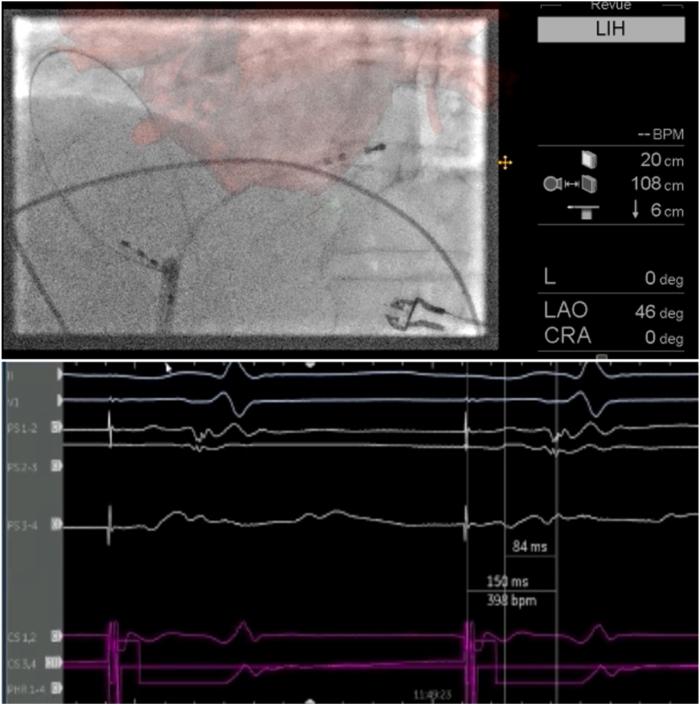

Linear cavotricuspid isthmus ablation with a circular pulsed-field catheter.

HeartRhythm Case Rep. 2025 Feb 12;11(5):429-431. doi: 10.1016/j.hrcr.2025.02.007. eCollection 2025 May.